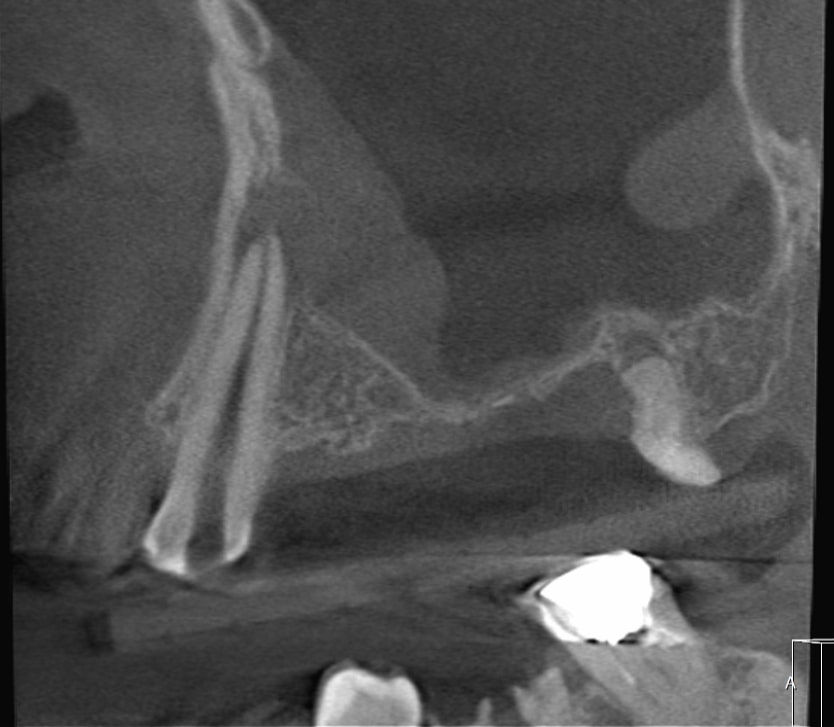

症例1歯性上顎洞炎(副鼻腔炎)

Before

歯性上顎洞炎(副鼻腔炎)

根尖病巣により、隣接する副鼻腔の膜がラッパ状に破れてしまい、全域に渡り粘膜が肥厚してしまっている。